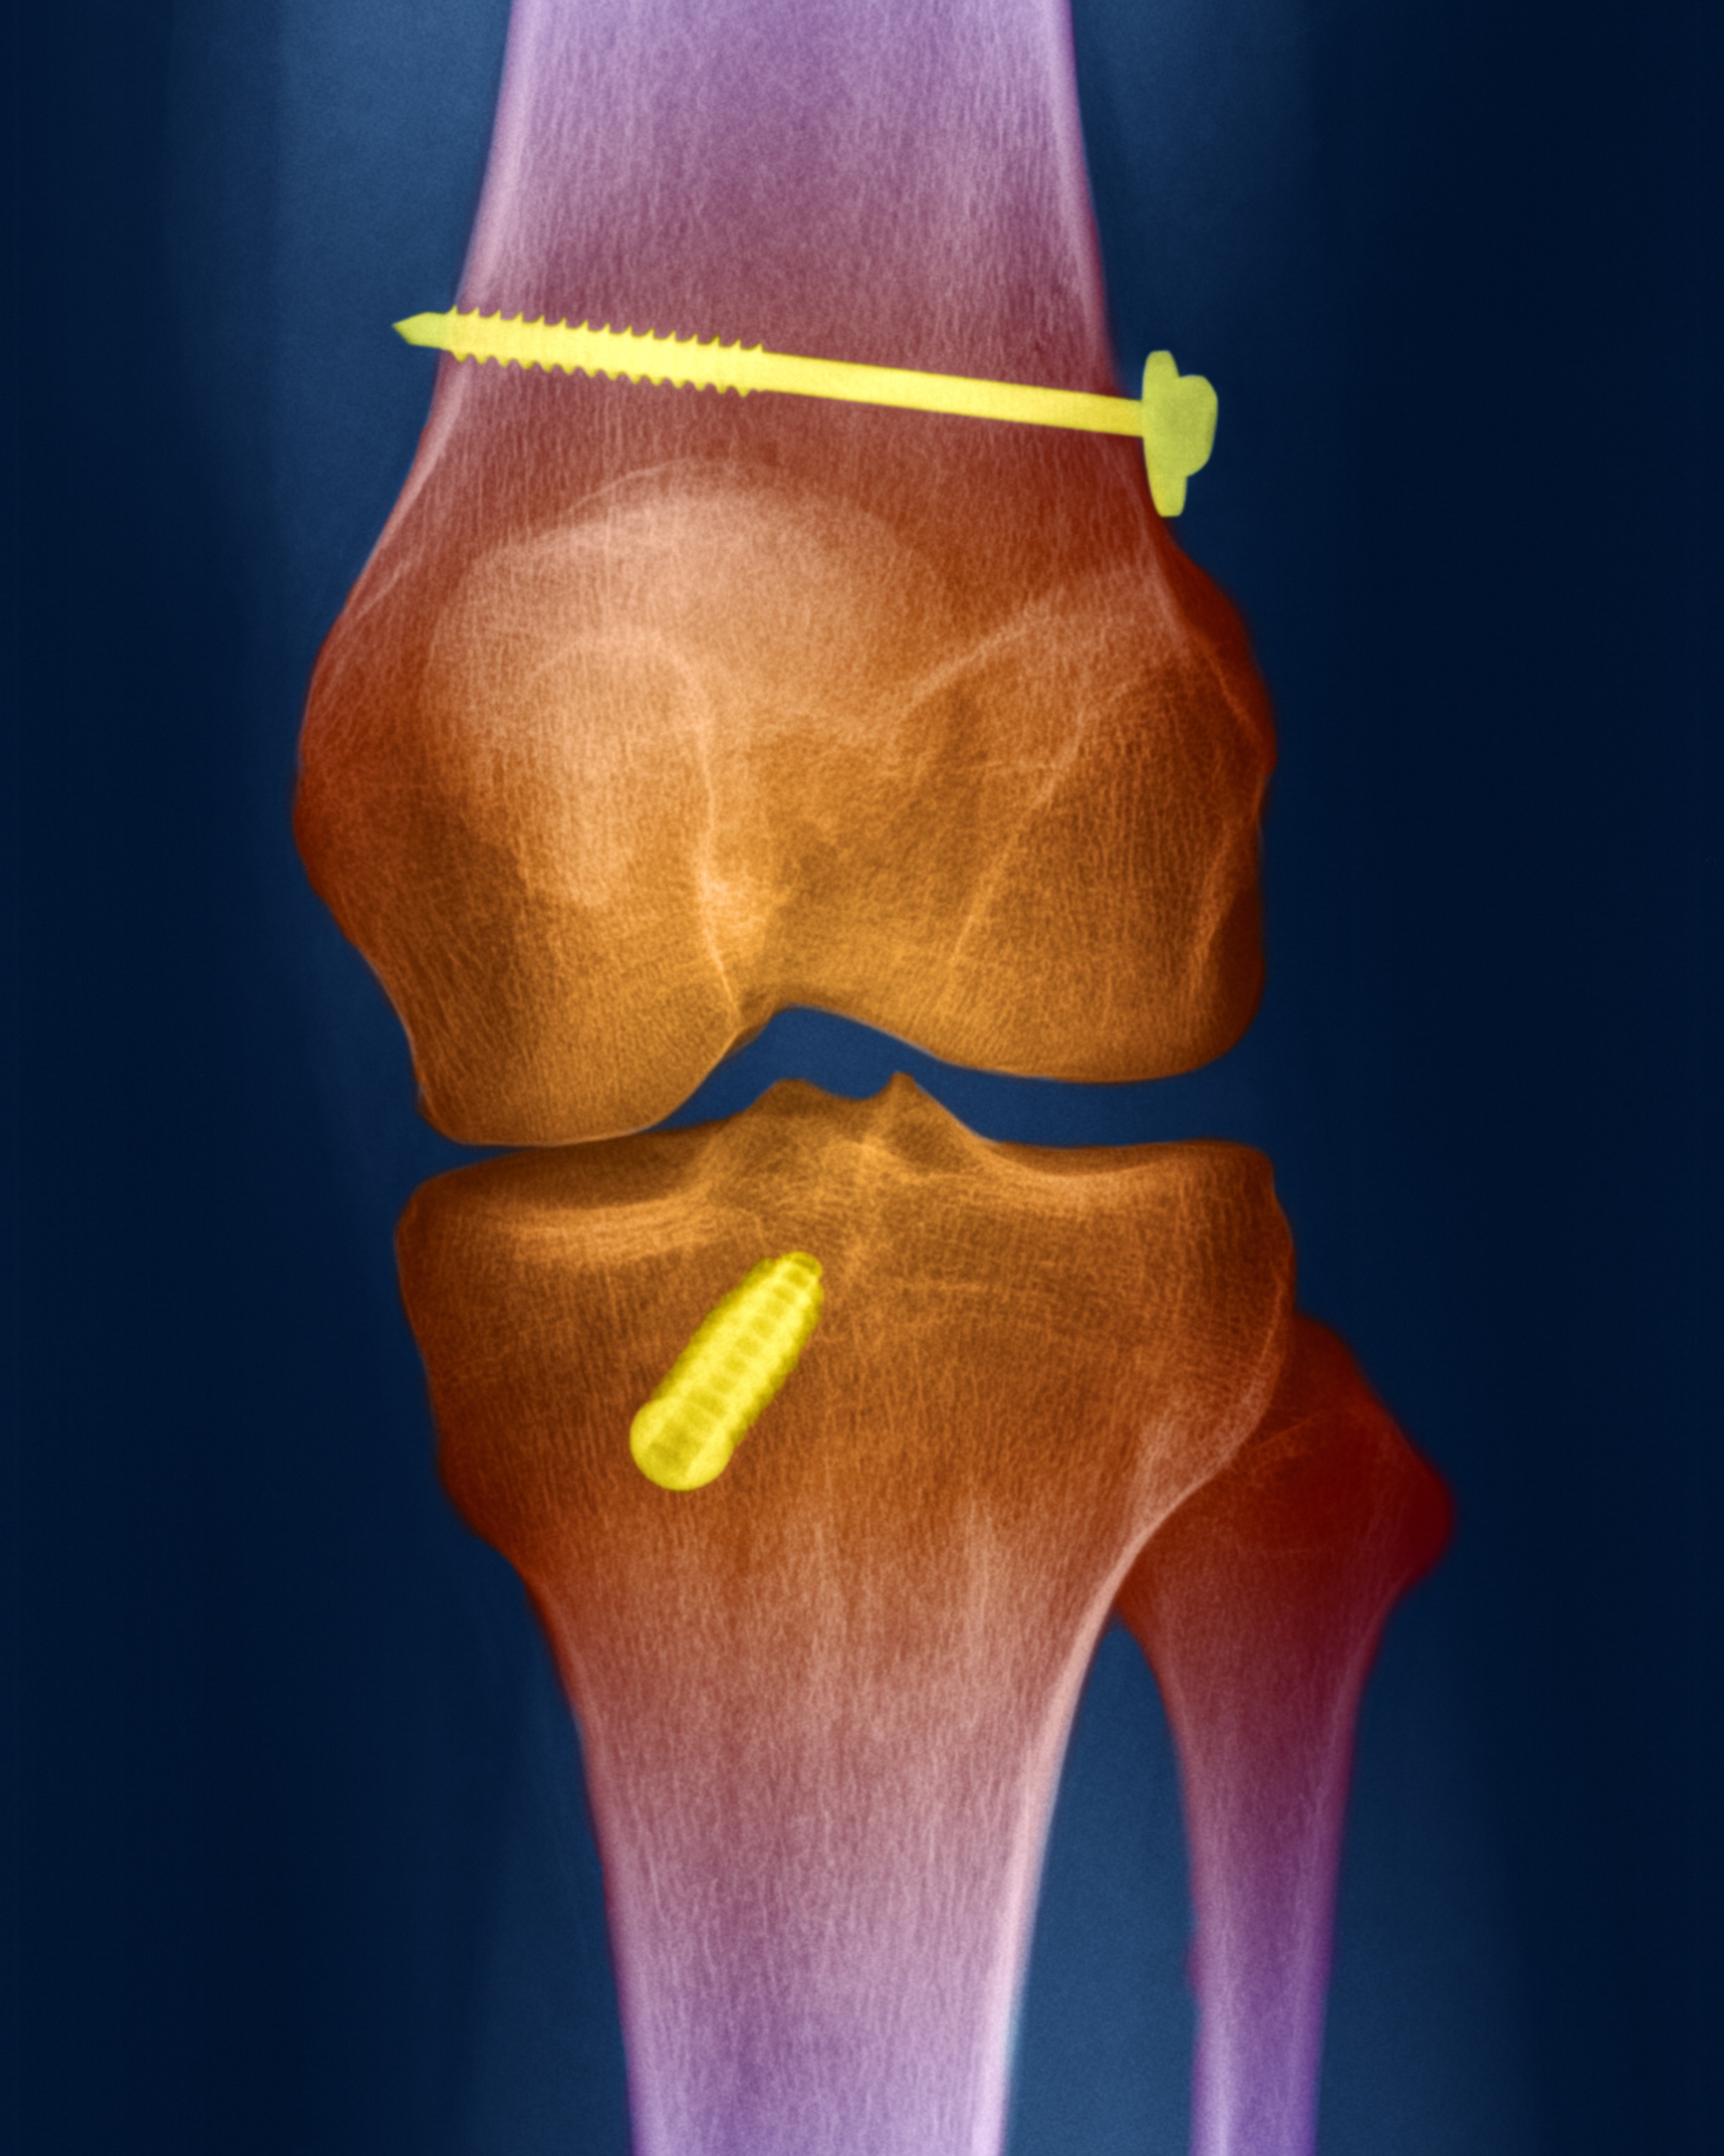

It's high time that ACL tears in girls are women are taken more seriously. An ACL tear can wreak havoc on girl’s and women’s bodies and minds and can be potentially career-ending for elite athletes. When the ACL is completely ruptured, the “gold standard” is surgery, according to Dr. Sara Edwards, an orthopedic surgeon at UCSF’s Women’s Sports Center, usually followed by nine to twelve months of extensive physical therapy. Females are at a higher risk of re-injury and it “can become a lifelong issue,” Edwards says. Kitley remembers, “it's such a long process. . . For me, I missed my last NCAA tournament, and I missed my ACC tournament and then had to be on crutches at the WNBA draft and then couldn't walk for a while. It completely consumes your life and still dealing with new stuff almost two years later is really frustrating.”